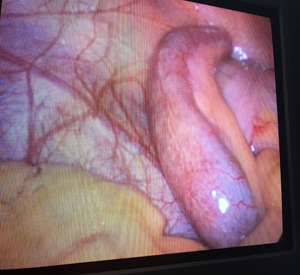

At Remedy Hospital we offer surgery for all conditions of appendix like appendicitis, appendicular malignancy, and mucocele of appendix. We offer surgery by latest technique (Laparoscopic Appendectomy) as well as time tasted conventional technique (Open Appendectomy).